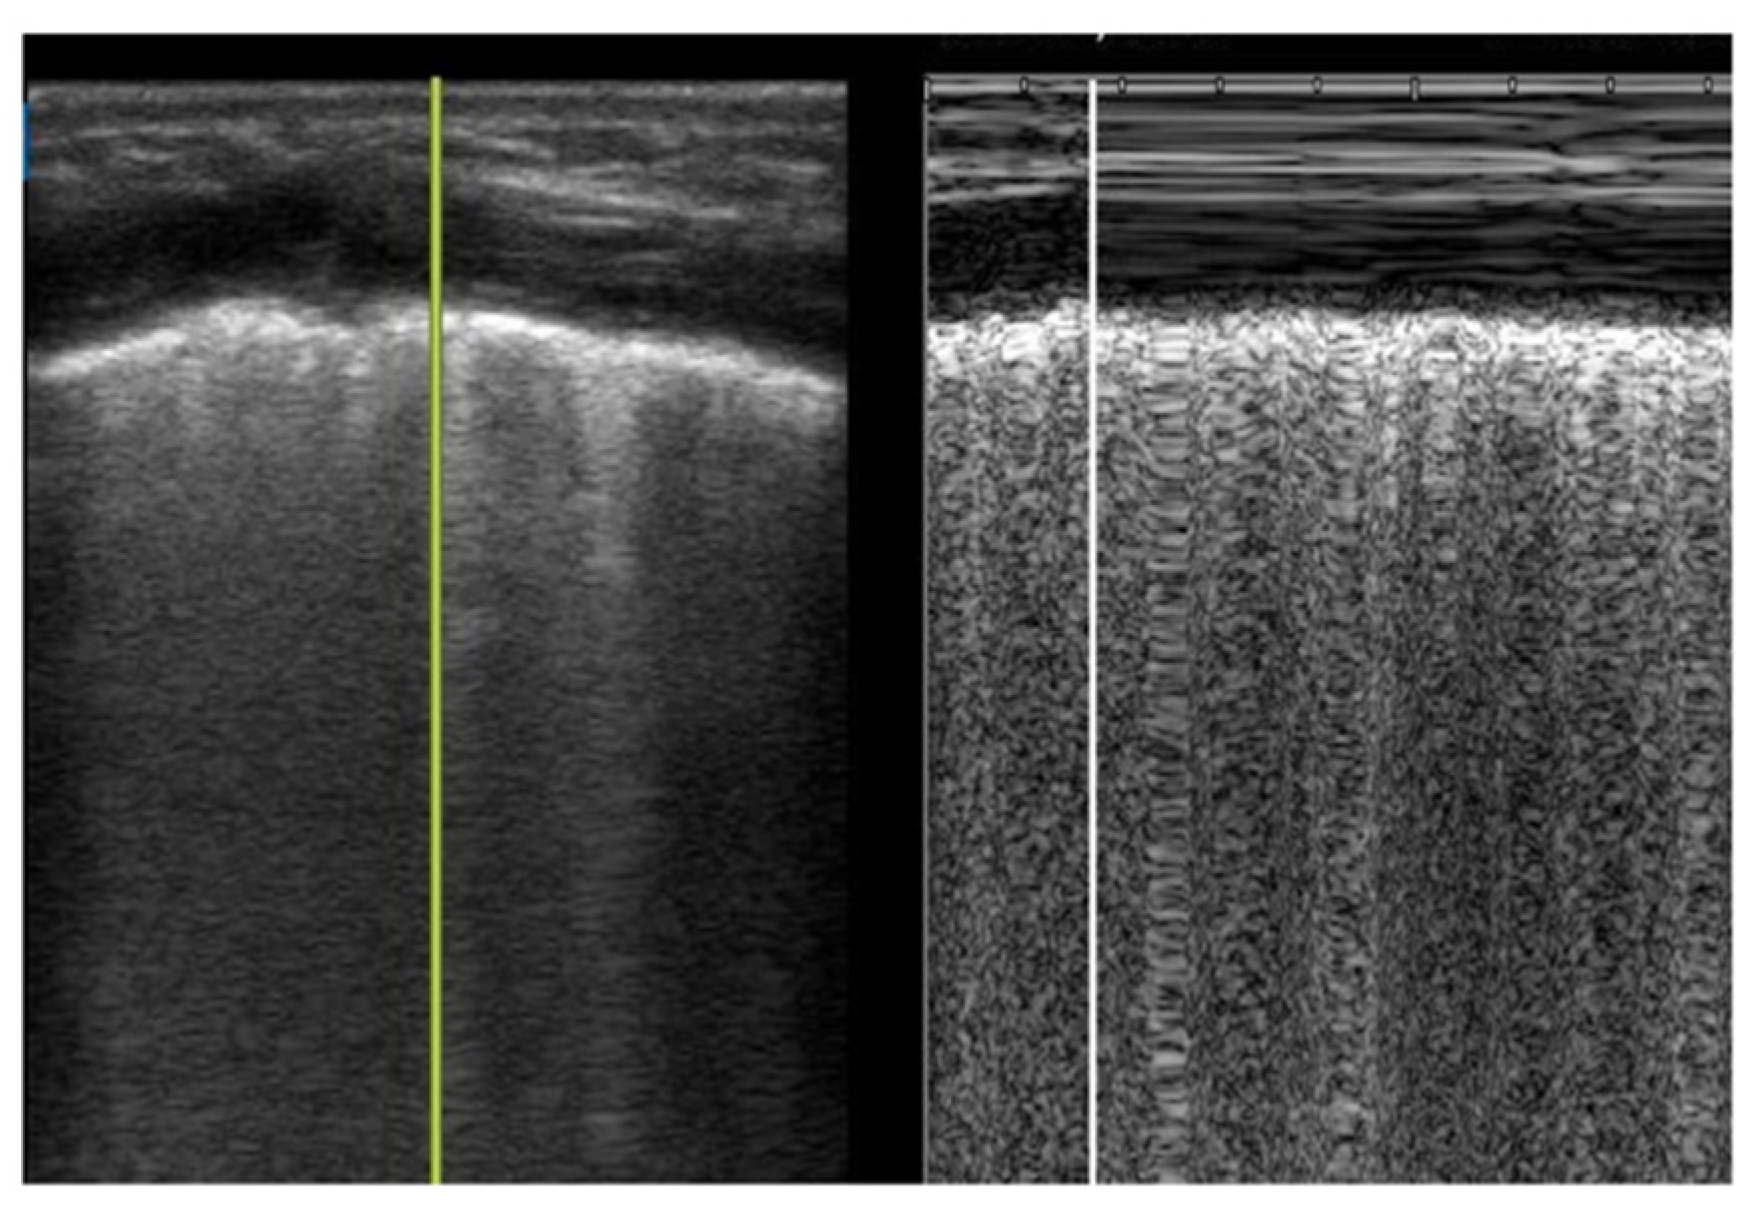

Lung sliding represents the sliding of the visceral and parietal pleura with respiration and can be visualized in B-mode or M-mode. In B-mode, lung sliding is described as the movement of ants marching along the pleural line with respiration (Supplementary Materials Video 1A,B). In M-mode, lung sliding appears as the seashore sign, where the static structures above the pleural line are the sea, and the movement below the pleural line creates the granularity of a sandy shore (Figure 3). Absent lung sliding can be encountered in any condition that affects the interpleural space, including pneumothorax, pleuropneumonia, complete atelectasis, and severe hyperinflation, as visualized through foreign body aspiration [20].

Figure 3. Lung sliding in M-mode. Very low birthweight infant with respiratory distress syndrome with normal lung sliding (seashore sign).